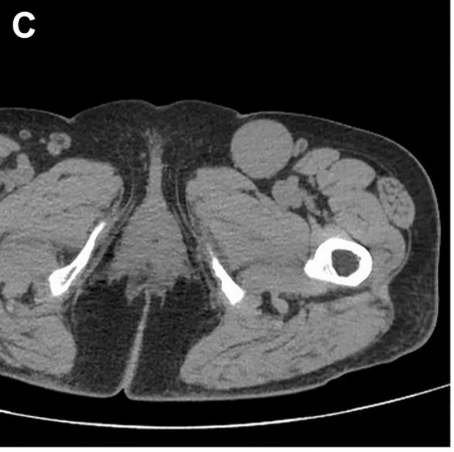

Better visualization, smarter planning. In this JVS-VL pilot study, CEUS + UHFUS showed promise for improving preop mapping and streamlining LVA in patients with lymphedema.